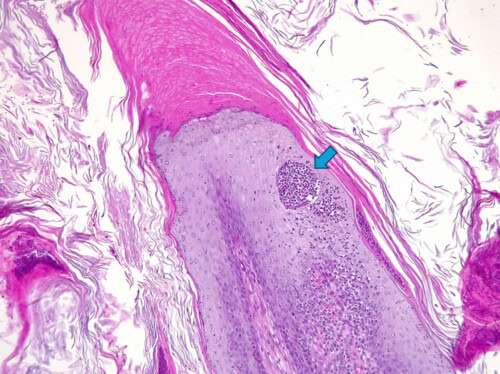

Photo 11 : Détail d’une autre papille épidermique. Notez l’épaisse coiffe de kératine orthokératosique compacte à son sommet (hyperkératose), l’hyperkératose environnante et les croûtes. Le détail le plus intéressant ici est cette petite collection de neutrophiles au sein de l’épiderme (pustule) de forme très ronde, enchâssé dans la couche épineuse (flèche). Cette pustule particulière est appelée « micro-abcès de Munro », un terme emprunté à la dermatopathologie humaine. En dermatologie humaine cette pustule particulière est une lésion élémentaire observée lors de psoriasis.

Photo 12 : Sur cette autre photo on peut à nouveau observer un micro-abcès de Munro (flèche). On peut également remarquer l’intense inflammation développée dans le derme juste sous l’épiderme. Cette inflammation formant une bande superficielle, marquée ici, est encore appelée « lichénoïde » par de nombreux pathologistes vétérinaires même si ce terme tend progressivement à disparaître des publications les plus récentes, considéré comme désuet et inadapté. Le mot « lichénoïde » est en effet un terme relativement ancien provenant de la pathologie humaine et correspondant à l’aspect de l’inflammation du derme dans les biopsies de « lichen plan ».